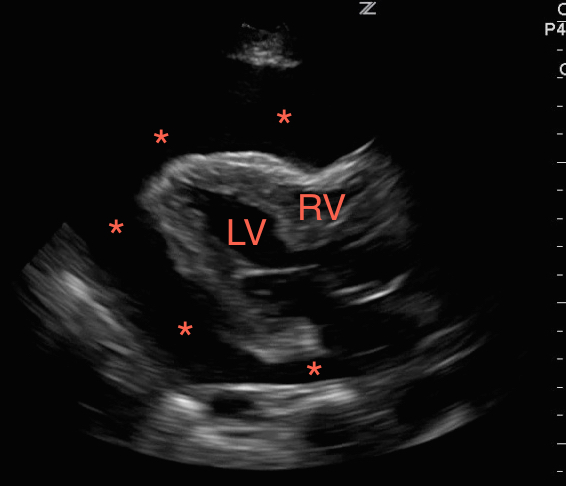

First, look at the heart. Evaluate for a pericardial effusion to rule out tamponade. If there is a pericardial effusion, view the heart in multiple windows including sub-xiphoid, parasternal long, parasternal short, and the apical four chamber to evaluate for right ventricular collapse during diastole as sonographic evidence of tamponade.[8] If you are having difficulty appreciating systole versus diastole, try using M-Mode. Point the beam over the anterior leaflet of the mitral valve in the parasternal long axis. With this image you can easily appreciate mitral valve opening during diastole as it swings up towards the inter-ventricular septum. The right ventricular free wall will be visible as a hyperechoic line between the outer anechoic pericardial effusion and inner anechoic blood within the right ventricle. When the mitral valve opens, diastole is occurring and you can easily appreciate right ventricular wall collapse into the right ventricle.

Figure 1. A large pericardial effusion (*) with tamponade physiology, right ventricular collapse during diastole.